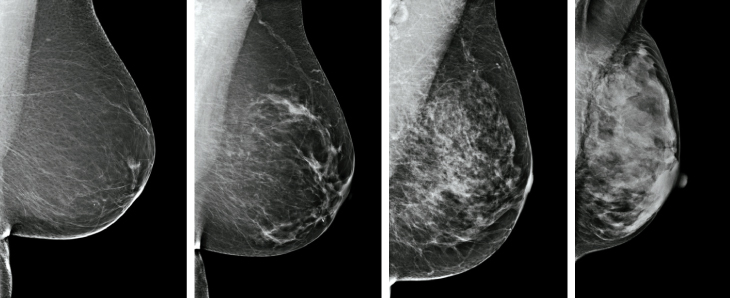

The Swiss researchers and others point out that all the assumptions about harms and benefits could be based on flawed data. The clinical trials used in evaluating the benefits of mammography began decades ago — which poses a problem of how applicable these studies are today. The quality of mammography technology used in a large Canadian trial was largely disparaged in February when the study, appearing in BMJ, reported that mammography offered no improvement in mortality rates for women ages 40 to 59. A statement issued by the Society of Breast Imaging and the American College of Radiology said the machines used in the study were secondhand, and rendered cloudy images. Writing in April in Cancer Control, a journal published by the Moffitt Cancer Center in Tampa, Fla., Jennifer Drukteinis and John Kiluk further seized on this point, charging that “the equipment used for mammography screening was of poor quality and was not state-of-the-art at the time, a fact that may account for the low percentage of cancers detected by screening.”